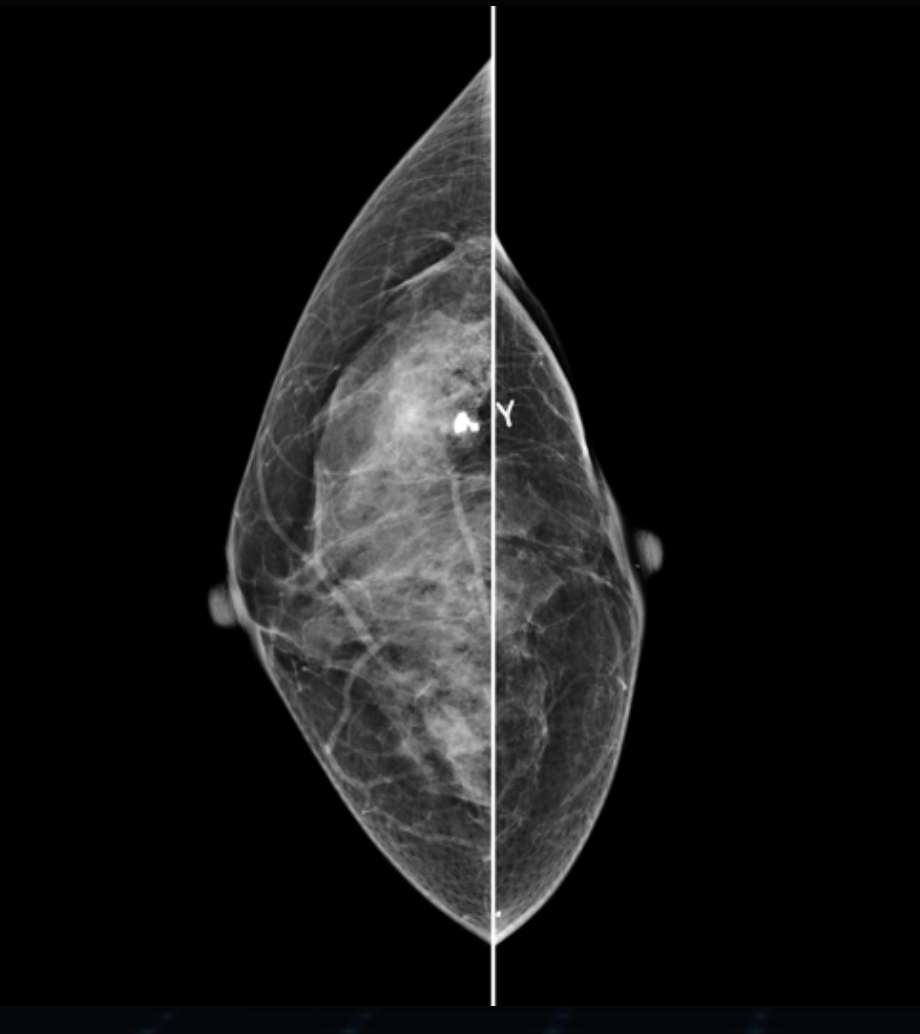

Detektor cyfrowy FFDM

Nowoczesny detektor cyfrowy o wysokiej czułości i rozdzielczości, zapewnia precyzyjne odwzorowanie detali anatomicznych, w tym mikrozwapnień i zmian strukturalnych miąższu.

Tomosynteza 3D

Hestia została zaprojektowana jako system modułowy, który umożliwia rozbudowę o tomosyntezę piersi – warstwowe obrazowanie 3D, zwiększające wykrywalność zmian.